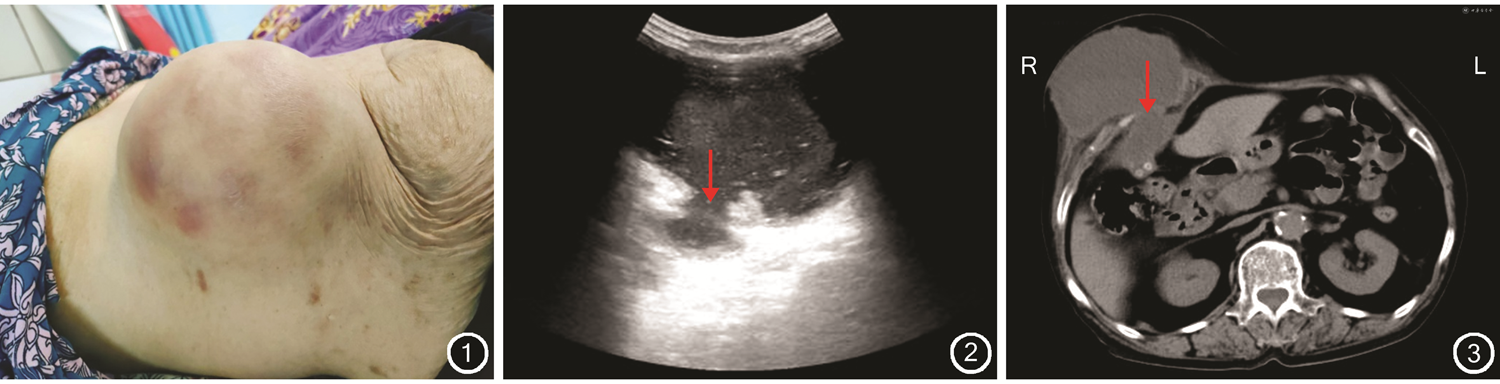

患者女,85岁,2022年6月因右侧腹壁包块反复发热伴有轻度疼痛半月入院。2022年4月患者家属发现患者右侧腹壁有一包块,无腹痛、腹胀等不适,未予重视,随后包块逐渐增大。体格检查结果显示右侧腹壁可触及长径约10 cm包块,质地柔软,边界清楚,表面皮肤红肿,轻压痛,无波动及搏动(图1)。超声检查结果显示右侧腹壁可见约98 mm×85 mm不均质混合回声包块,内部透声差,其内充满密集点状回声及强回声伴声影,加压探头可见流动,腹壁连续性中断可见瘘口与腹腔相通(图2);肝胆超声检查结果显示未见正常胆囊图像;彩色多普勒血流显像检测结果显示包块内未见彩色血流信号。超声检查诊断为右侧腹壁囊性包块(胆囊结石、胆囊腹壁瘘不排除),建议进一步检查。腹部CT检查结果显示胆囊疝伴多发结石、炎症可能(图3)。

徐中亚主治医师:患者因腹部包块就诊检查,超声检查结果右侧腹壁囊性包块(胆囊结石,胆囊腹壁瘘不排除);CT检查平扫结果示右侧腹腔及腹壁囊性占位性病变。考虑胆囊疝伴多发结石、炎症可能,结合临床,患者诊断胆囊腹壁外瘘。